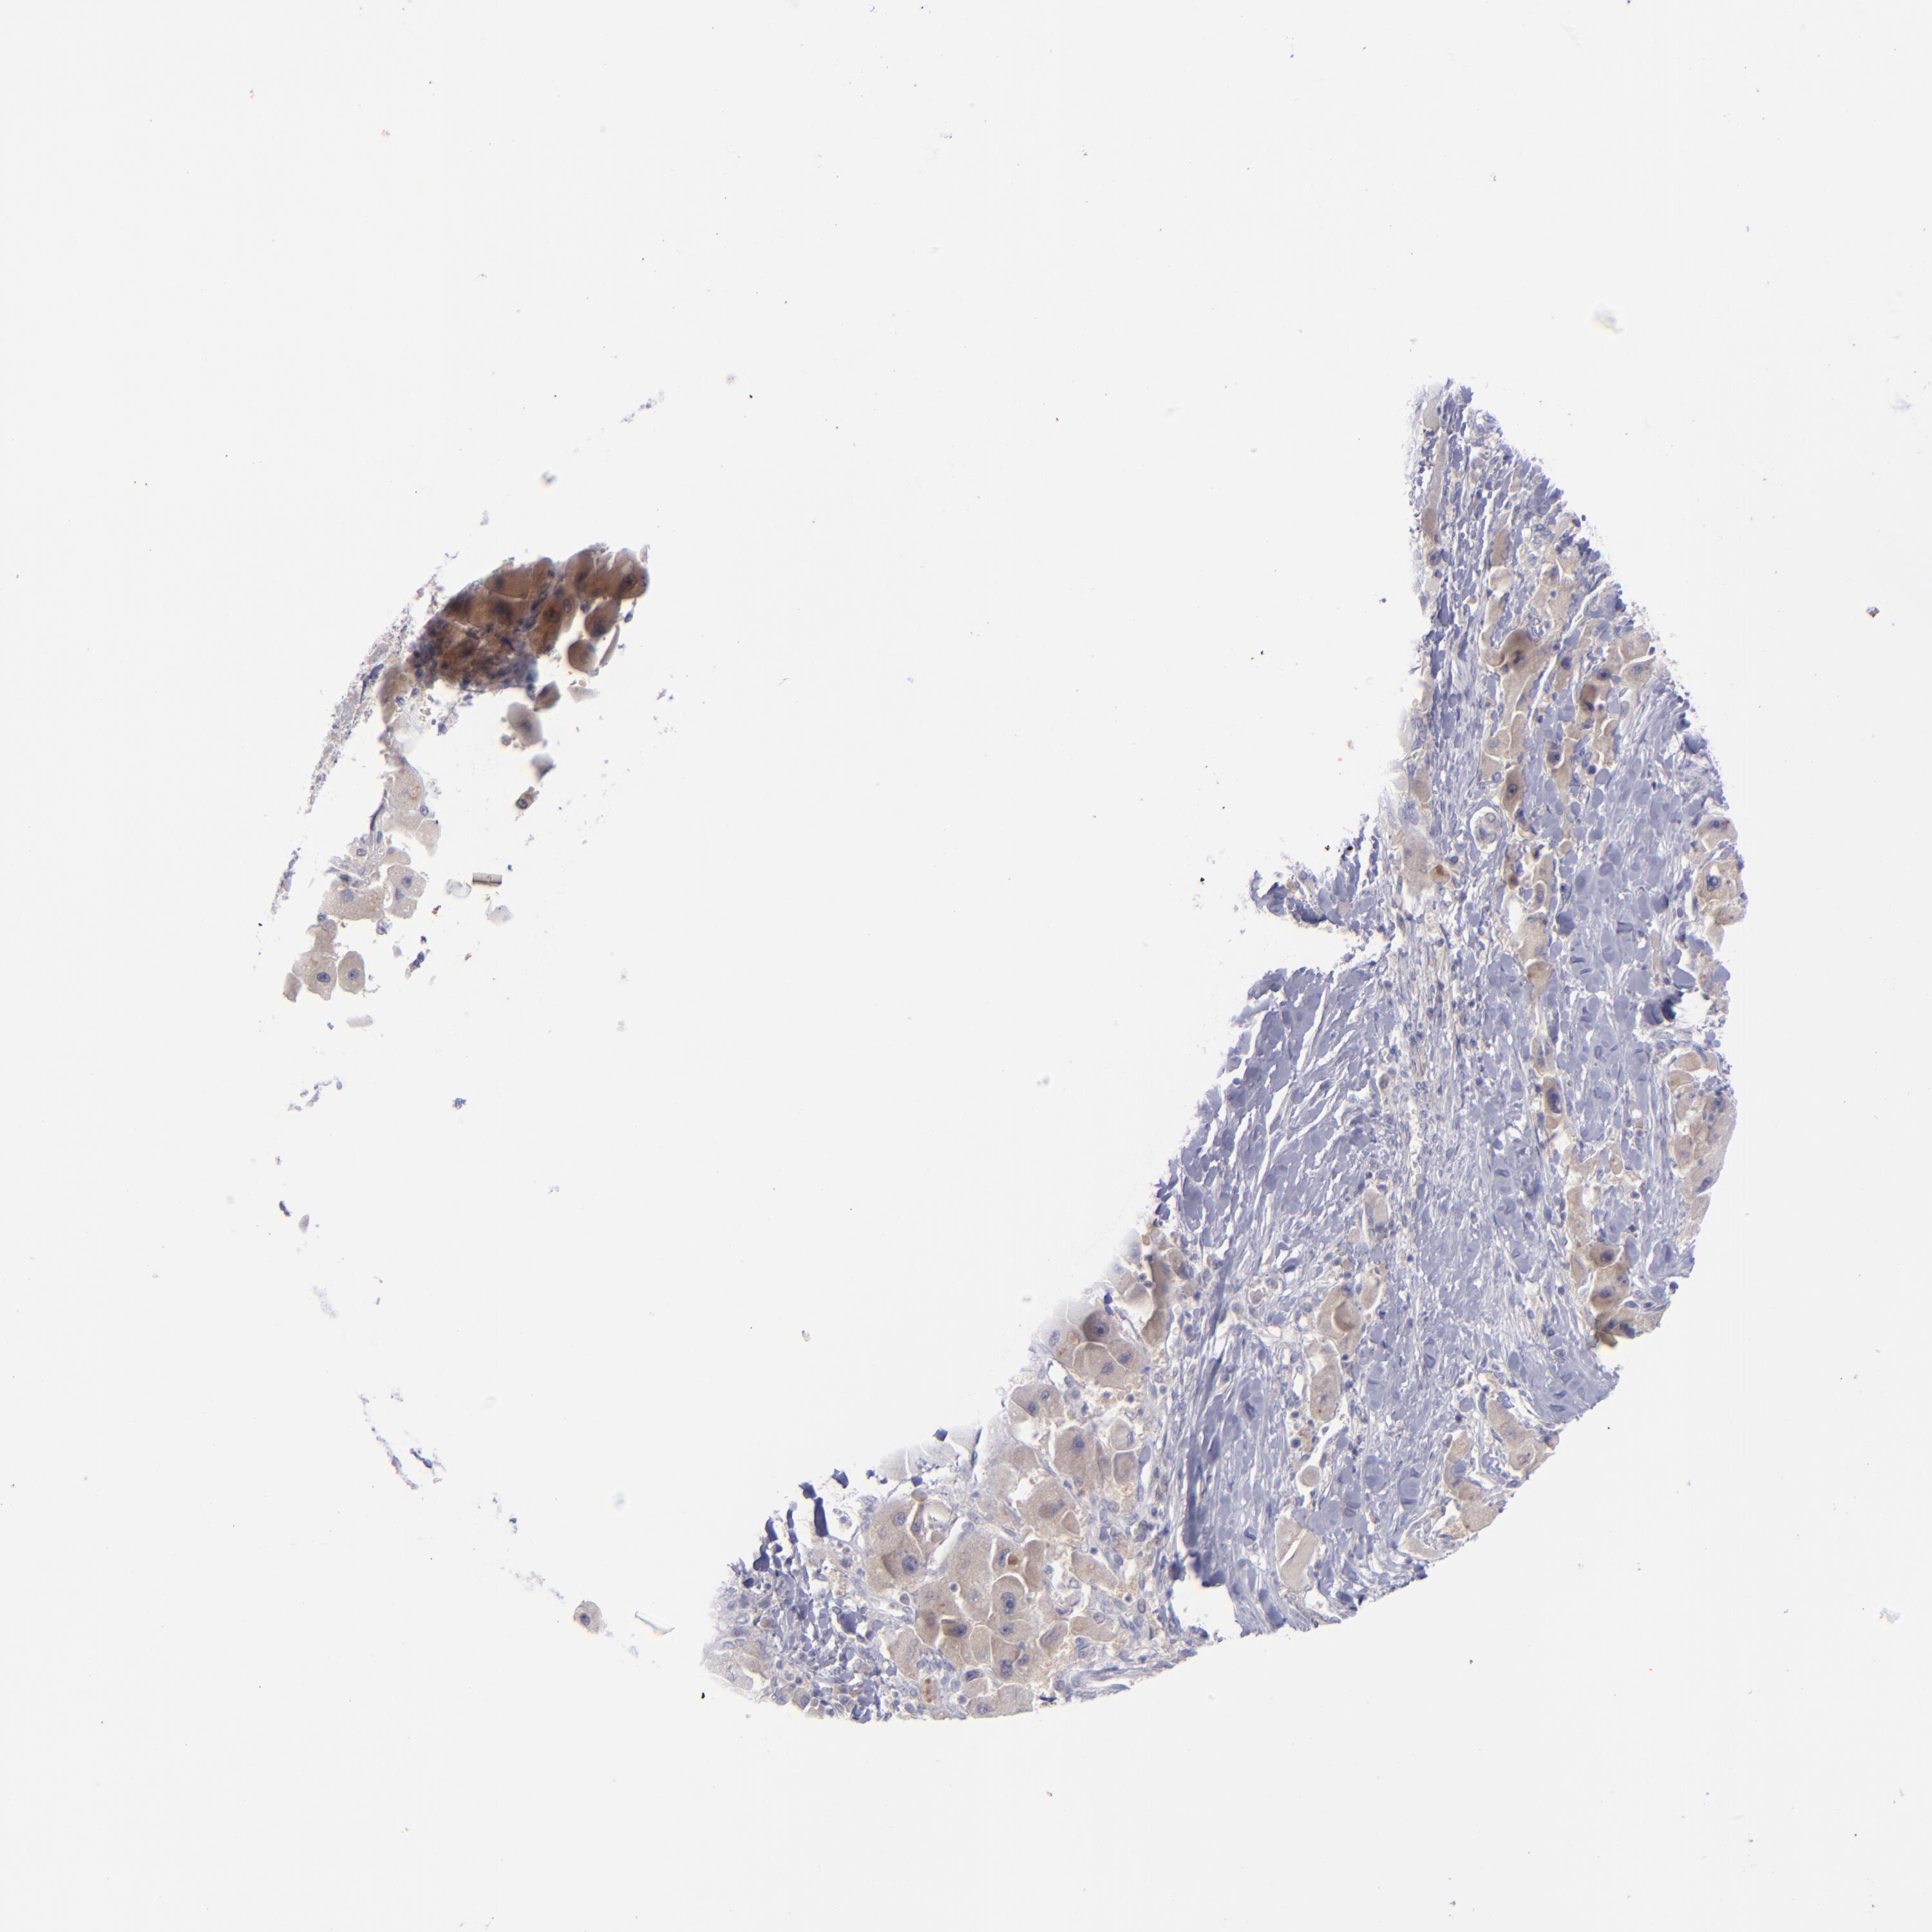

LIVER CANCER - Protein expressioni

A mouse-over function shows sample information and annotation data. Click on an image to view it in a full screen mode. Samples can be filtered based on level of antibody staining by selecting one or several of the following categories: high, medium, low and not detected. The assay and annotation is described here.

Note that samples used for immunohistochemistry by the Human Protein Atlas do not correspond to samples in the TCGA dataset.

Antibody stainingi

Antibody staining in the annotated cell types in the current human tissue is reported as not detected, low, medium, or high, based on conventional immunohistochemistry profiling in selected tissues. This score is based on the combination of the staining intensity and fraction of stained cells.

Each image is clickable and will lead to virtual microscopy that enables deeper exploration of all samples and also displays staining intensity scores, fraction scores and subcellular localization as well as patient and tissue information for each sample.

Antibody HPA053969

Staining

High

Medium

Low

Not detected

Intensity

Strong

Moderate

Weak

Negative

Quantity

>75%

75%-25%

<25%

None

Location

Nuclear

Cytoplasmic/membranous

Cytoplasmic/membranous,nuclear

Carcinoma, Hepatocellular, NOS

Cholangiocarcinoma